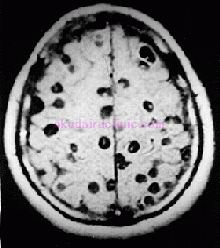

ただし寄生虫がみな大人しいかと言いますとそんなことはなく、有鉤条虫という別のサナダムシは厄介なので駆除する際には注意が必要です。虫下しを服用するとサナダムシ自体はあっけなく死んでしまうのですが、運悪く死んだ虫体の体内にあった卵が小腸内にばらまかれると、大量の幼虫が腸管内に遊出してくることになります。幼虫は腸管壁から体内に潜り込み、血管に迷入すると脳を含めた他臓器に転移し、下の図3のように有鉤嚢虫症を形成することがあります。もう、全くもってホラーの世界です。